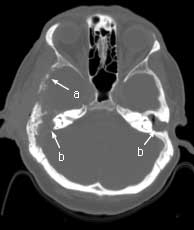

Axial CT bone windows

Findings:

Extensive, permeative destruction involving the squamous portion of the right temporal bone (a). Post-op bilateral mastoidectomies (b).